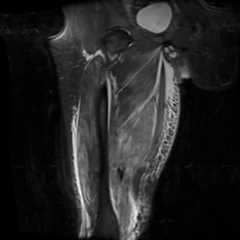

Figure 2d.

Coronal STIR image of the right thigh in coronal planes demonstrating extensive high signal abnormality in the adductor, anterior, and posterior compartments, representing edema and ischemia from alprazolam microembolism. [Powerpoint Slide]